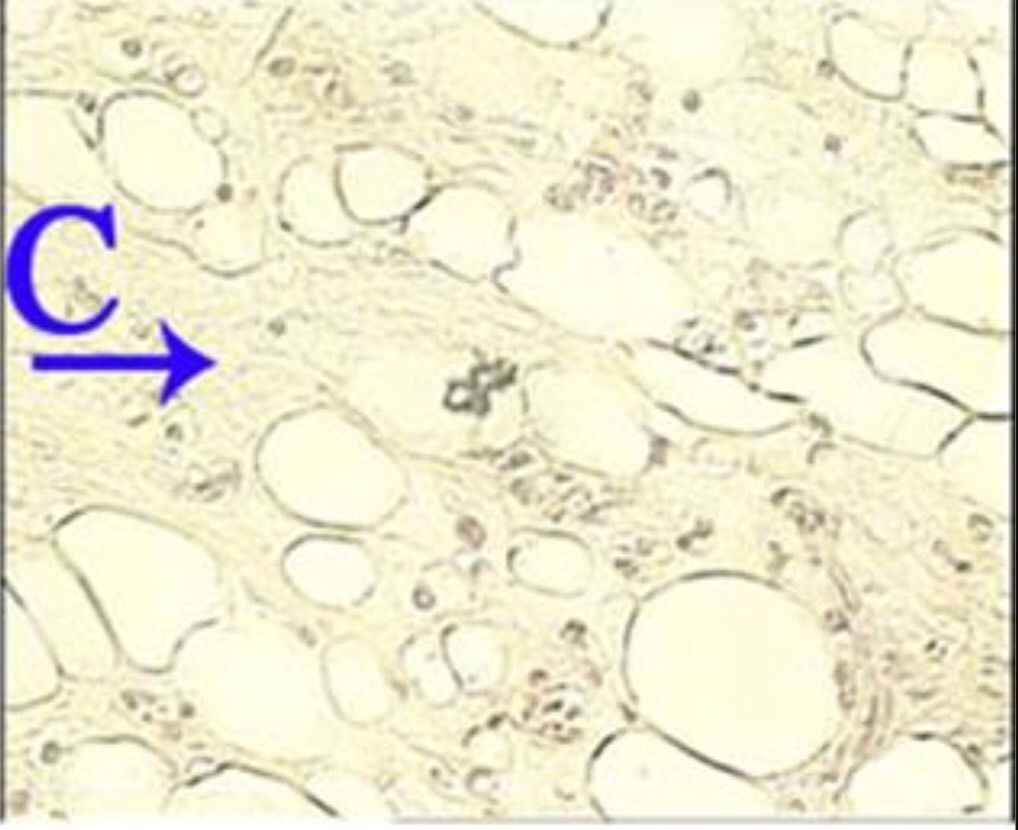

What is the correct answer at point C?

Answer

• - peau et ses annexes

• - tissu adipeux

• - tissu de la glande thyroïde

• - cartilage

• - glande sébacé